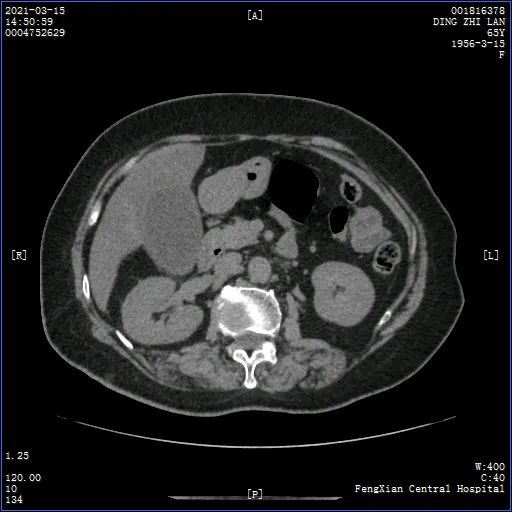

因为上腹部疼痛伴高热2天,丁阿姨被我院急诊外科拟急性胆囊炎后收治

胆囊体积增大壁增厚,典型双边征,明确诊断后,请示陈主任,果断建议行

胆囊壁呈双边征改变,并可见宽基底占位性病变

胆囊炎的超声特点是双边征(因为炎症导致胆囊壁水肿所致),胆囊壁增厚

胆囊体积增大,囊壁增厚呈"双边影". 2.囊内可见细密光点或斑片状回声.

3. 双边征

4cm,常有双边征.对提示胆囊炎有较大价值.